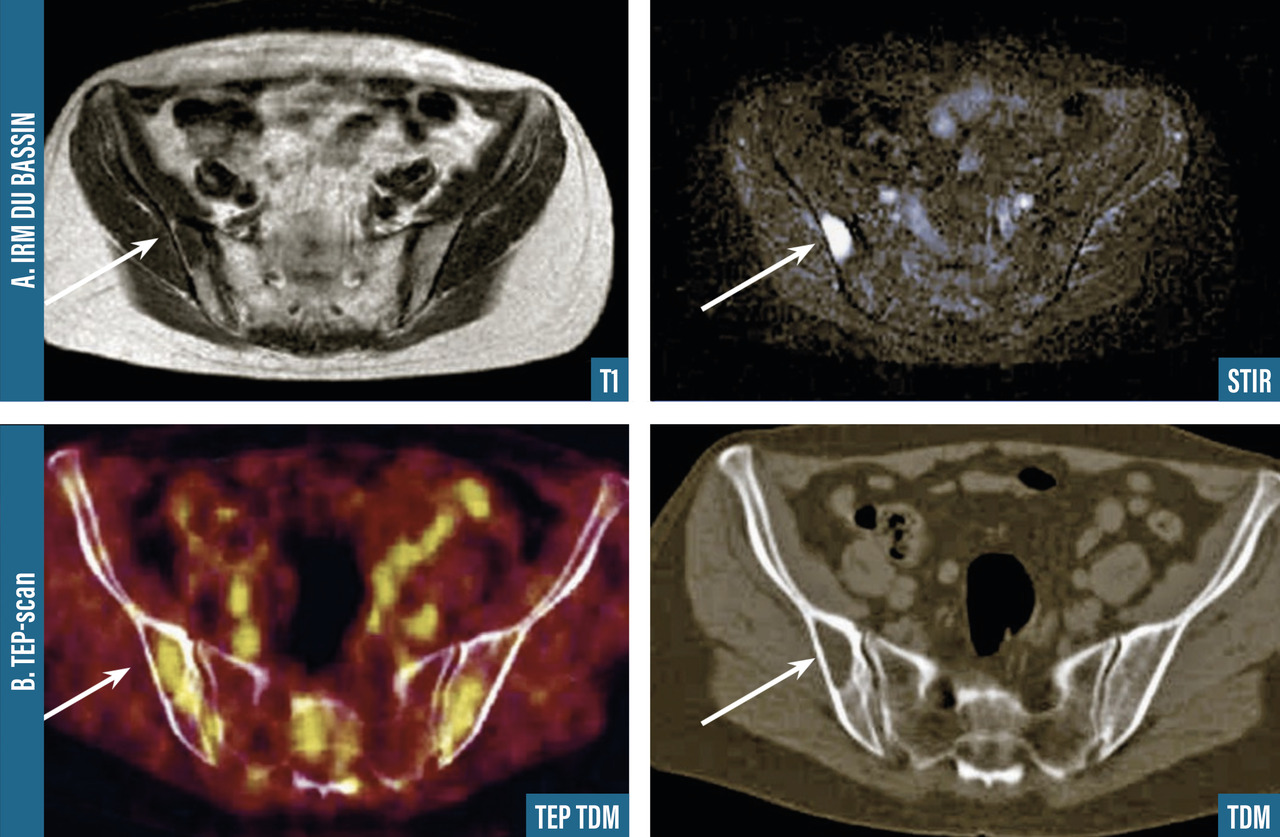

Les clichés standard du squelette axial (crâne, rachis, côtes et bassin) restent encore la référence pour diag­nostiquer une atteinte osseuse mais devraient être remplacés, en raison de leur faible sensibilité, par l’imagerie moderne. Les anomalies évocatrices sont une lyse à l’emporte-pièce (géode ou lacune), visible sur les os plats, associée ou non à une déminéralisation diffuse, ou sur les os longs avec résorption corticale et menace de fracture pathologique (fig. 4). Les lacunes peuvent être totalement asymptomatiques, notamment lorsqu’elles siègent sur le crâne. Les tassements vertébraux, plus ou moins complets, voire en galette, sont toujours symptomatiques. Le scanner du corps entier faible dose devrait remplacer les clichés standard en raison de sa plus grande sensibilité, de sa durée de réalisation plus courte et de sa plus faible dose délivrée d’irradiation. L’IRM du corps entier et le TEP-scan détectent 20 % de lésions supplémentaires par rapport aux clichés osseux standard sous la forme d’images nodulaires en hyposignal T1 et hypersignal T2 et STIR, pour l’IRM (fig. 5), ou de foyers hypermétaboliques correspondant aux lacunes sur le scanner, pour le TEP-scan (fig. 6). Ces examens sont particulièrement utiles dans les formes peu avancées de la maladie (absence d’anomalie sur les clichés standard), pour dépister une épidurite ou confirmer le caractère tumoral du tassement vertébral (IRM) et pour suivre l’évolution sous traitement (réponse métabolique au TEP-scan avec disparition des foyers hypermétaboliques). Leur utilisation est en cours de validation et limitée par leur accessibilité.